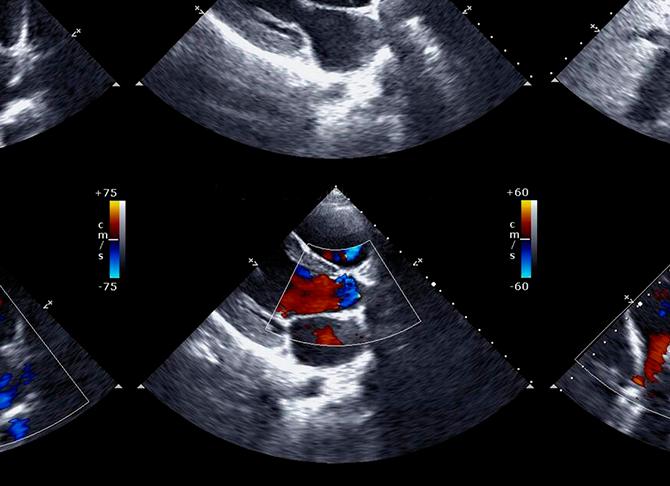

• цветовая допплерография. Позволяет оценить не только скорость, но и направление движения крови по магистральным сосудам. Применяется для оценки патологического кровотока через клапаны сердца.

• Режим цветного картирования потока. Метод применяется для выявления клапанных и турбулентных потоков в области локализации закупорки. Полученные данные выводятся на дисплей в виде цветного изображения, которое является схемой распределения скорости кровотока.

Метод цветного картирования (ЦДК) – это очень эффективное исследование, позволяющие произвести оценку состояния не только сосудов, но и выявить локализацию тромбов, атеросклеротических бляшек, а также аневризму аорты. Интерпретация данных помогает определить специалисту характер новообразования и темп его развития.

Современное развитие диагностических технологий позволяет визуализировать кровоток аорты в виде разноцветной картограммы. Во время цветного допплеровского картирования (ЦДК) цветовая гамма используется для детального отображения интенсивности и направленности кровотока.

Режим ЦДК позволяет наиболее полно оценить состояние сосудистой системы

Цветное допплеровское сканирование

Одним из наиболее важных и современных видов ЭхоКГ является цветная допплеровская эхокардиография. Изобретена она было недавно вследствие усовершенствования импульсной ЭхоКГ. Принцип ее состоит в получение двухмерного изображения сердца и измерения скоростей кровотока в нем. Затем участки, где кровь движется к датчику, окрашиваются в одни цвет, а где от него — в другой (как правило, красный и синий).

Цветное сканирование выявляет скорость кровотока, его направление, наличие турбулентности в потоке и искажения допплеровского спектра. Благодаря этому методу можно быстро получить результаты относительно пространственной ориентации потоков. А это позволяет оценивать регургитационную способность клапанов.